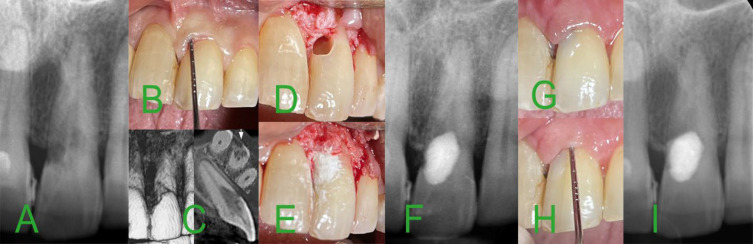

Invasive cervical root resorption (ICRR) is a rare and clinically complex condition marked by the progressive loss of dental hard tissues below the junctional epithelium. This case report outlines the management of a 32-year-old female patient presenting with ICRR class 3 affecting a maxillary incisor. Despite the absence of symptoms, the expansive nature of the defect warranted conservative surgical intervention. The procedure involved the surgical removal of inflamed tissues, followed by an ultraconservative modified pulpotomy utilizing calcium-enriched mixture (CEM) cement through a surgical window. The selected intervention is substantiated by its potential benefits, such as minimal removal of tooth structure and the inherent biocompatibility and sealing capabilities of CEM cement. A one-year follow-up revealed arrested resorption, re-establishment of periodontal attachment, and successful esthetic restoration, affirming the efficacy of vital pulp therapy in surgically addressing advanced ICRR. Accurate diagnosis, strategic treatment planning, and a patient-centered approach proved critical in achieving favorable outcomes.